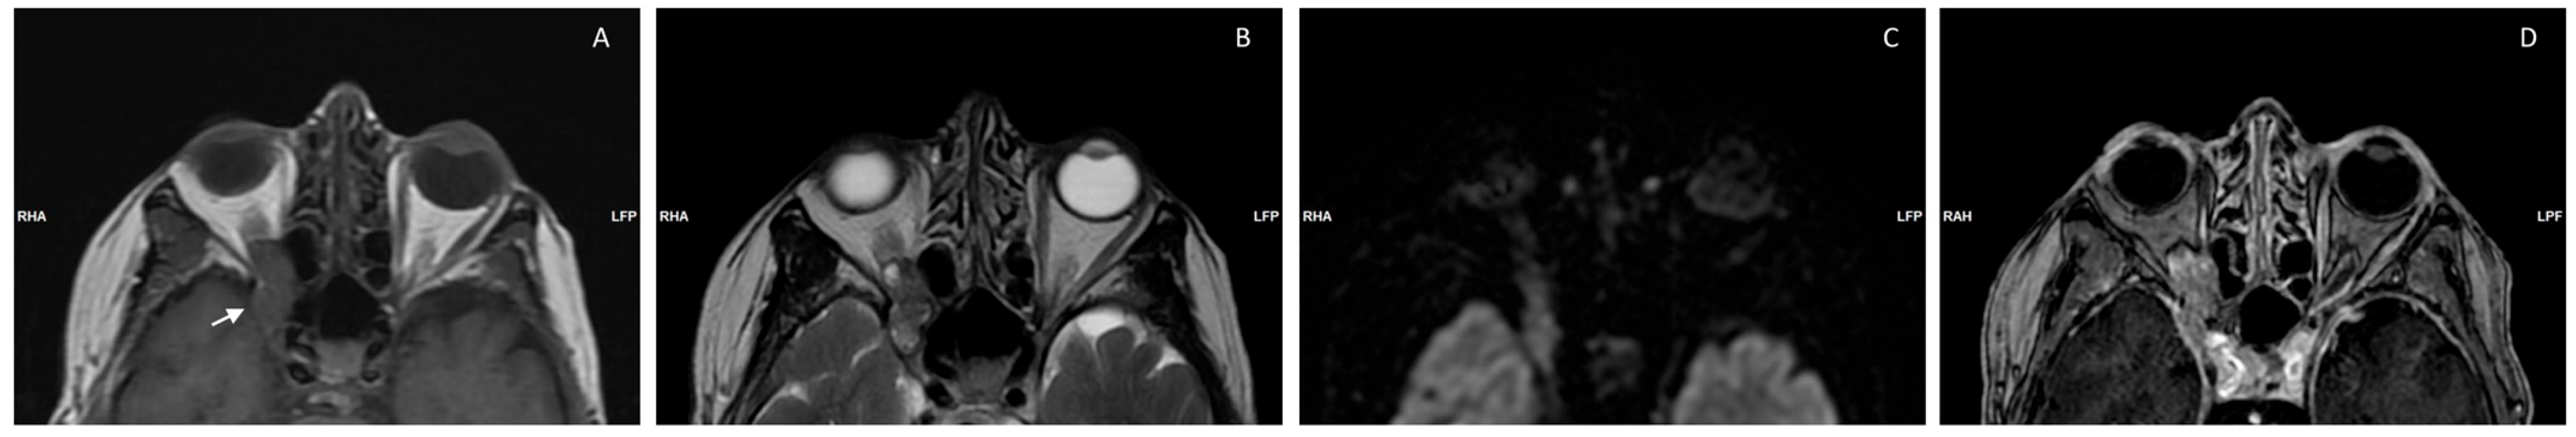

| Arrivi et al., 2023 (our case) | 77/F | Proptosis, loss of vision | PET-CT Ga-68 PET-CT 18-F, MRI, total body CT, CT Enterography Visual acuity exam | WD-NET G2 (Ki-67 6%) | WD-NET | Right Orbit | Lanreotide | OS 3 y |